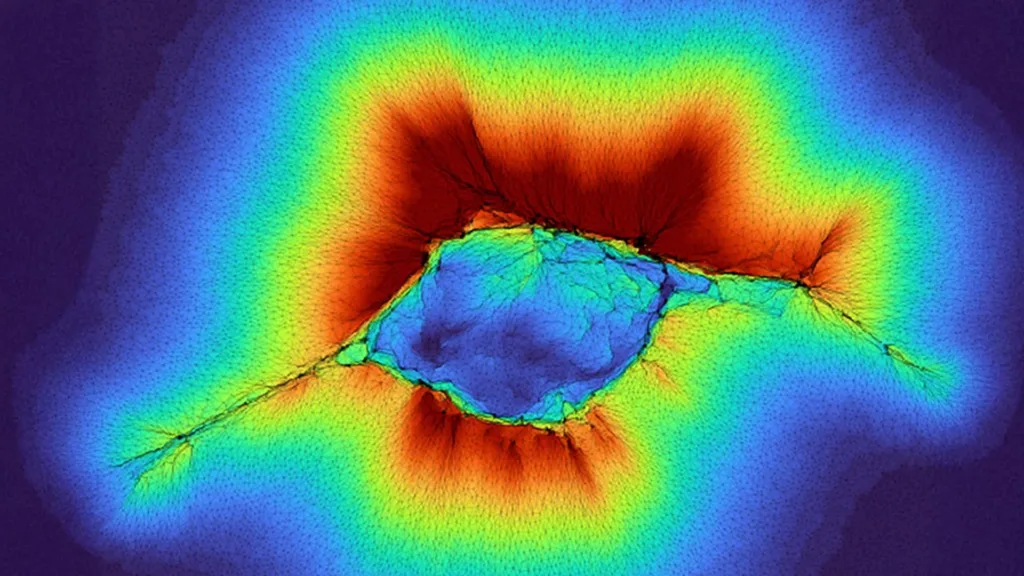

Cercetătorii WashU arată că grupurile de celule epiteliale pot percepe straturi aflate până la 100 μm distanță, iar descoperirea poate clarifica mecanismele migrației celulelor canceroase.

O echipă de cercetători de la Washington University in St. Louis a demonstrat că celulele pot percepe structuri aflate mult mai departe decât aria imediat contactată, iar această capacitate extinsă de detecție mecanică ar putea fi importantă pentru înțelegerea modului în care celulele canceroase se deplasează și se răspândesc prin țesuturi.

Rezultatele recente descrise de cercetători arată că atunci când celulele epiteliale — care alcătuiesc suprafețele multor organe — acționează în grup, ele pot genera forțe cumulativ mai mari și astfel pot „simți” straturi situate mult mai departe. Observațiile indică faptul că agregatele de celule epiteliale pot detecta straturi aflate la distanțe de până la 100 de microni.

Prin urmare, matricea de colagen funcționează nu doar ca suport structural, ci și ca mediu de transmitere a semnalelor mecanice între celule. Capacitatea unei singure celule anormale de a trage și remodela colagenul îi permite să simtă elemente aflate la aproximativ 10 microni; când multe celule trag în același timp, efectul cumulative al acestor forțe poate propaga semnale pe sute de microni, permițând observarea unui strat aflat la 100 de microni.